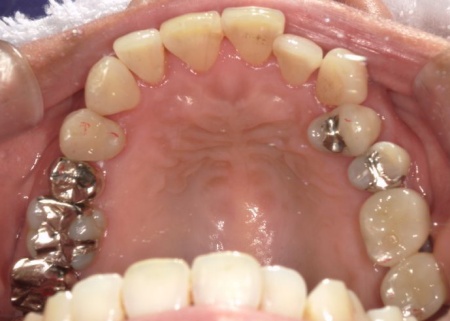

また、右下奥歯には、両隣の歯を土台にして橋を渡すように欠損部を補う被せ物「ブリッジ」が装着されていました。

右下奥歯は2本欠損しており、親知らず(第3大臼歯)と手前の奥歯(第2小臼歯)の2本でブリッジを支えていますが、これは親知らずに過度な負荷がかかる構造です。

親知らずはすでに大きく傾いており、こちらも温存が難しいため、ブリッジを除去してから親知らずを抜く必要があります。